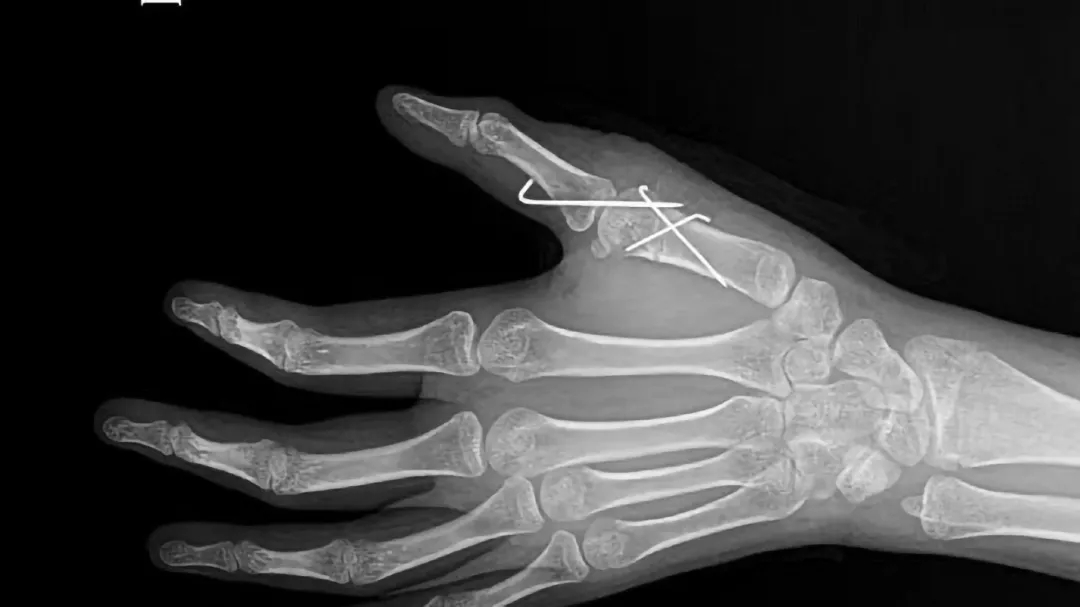

重庆红楼医院骨科汪主任团队凭借丰富的临床经验,历时3小时,成功完成左拇指多指切除术、第一掌骨截骨矫形术、掌指关节脱位复位内固定术、拇短展肌腱止点重建术、掌指关节囊、侧副韧带修复术等手术。

(术后)